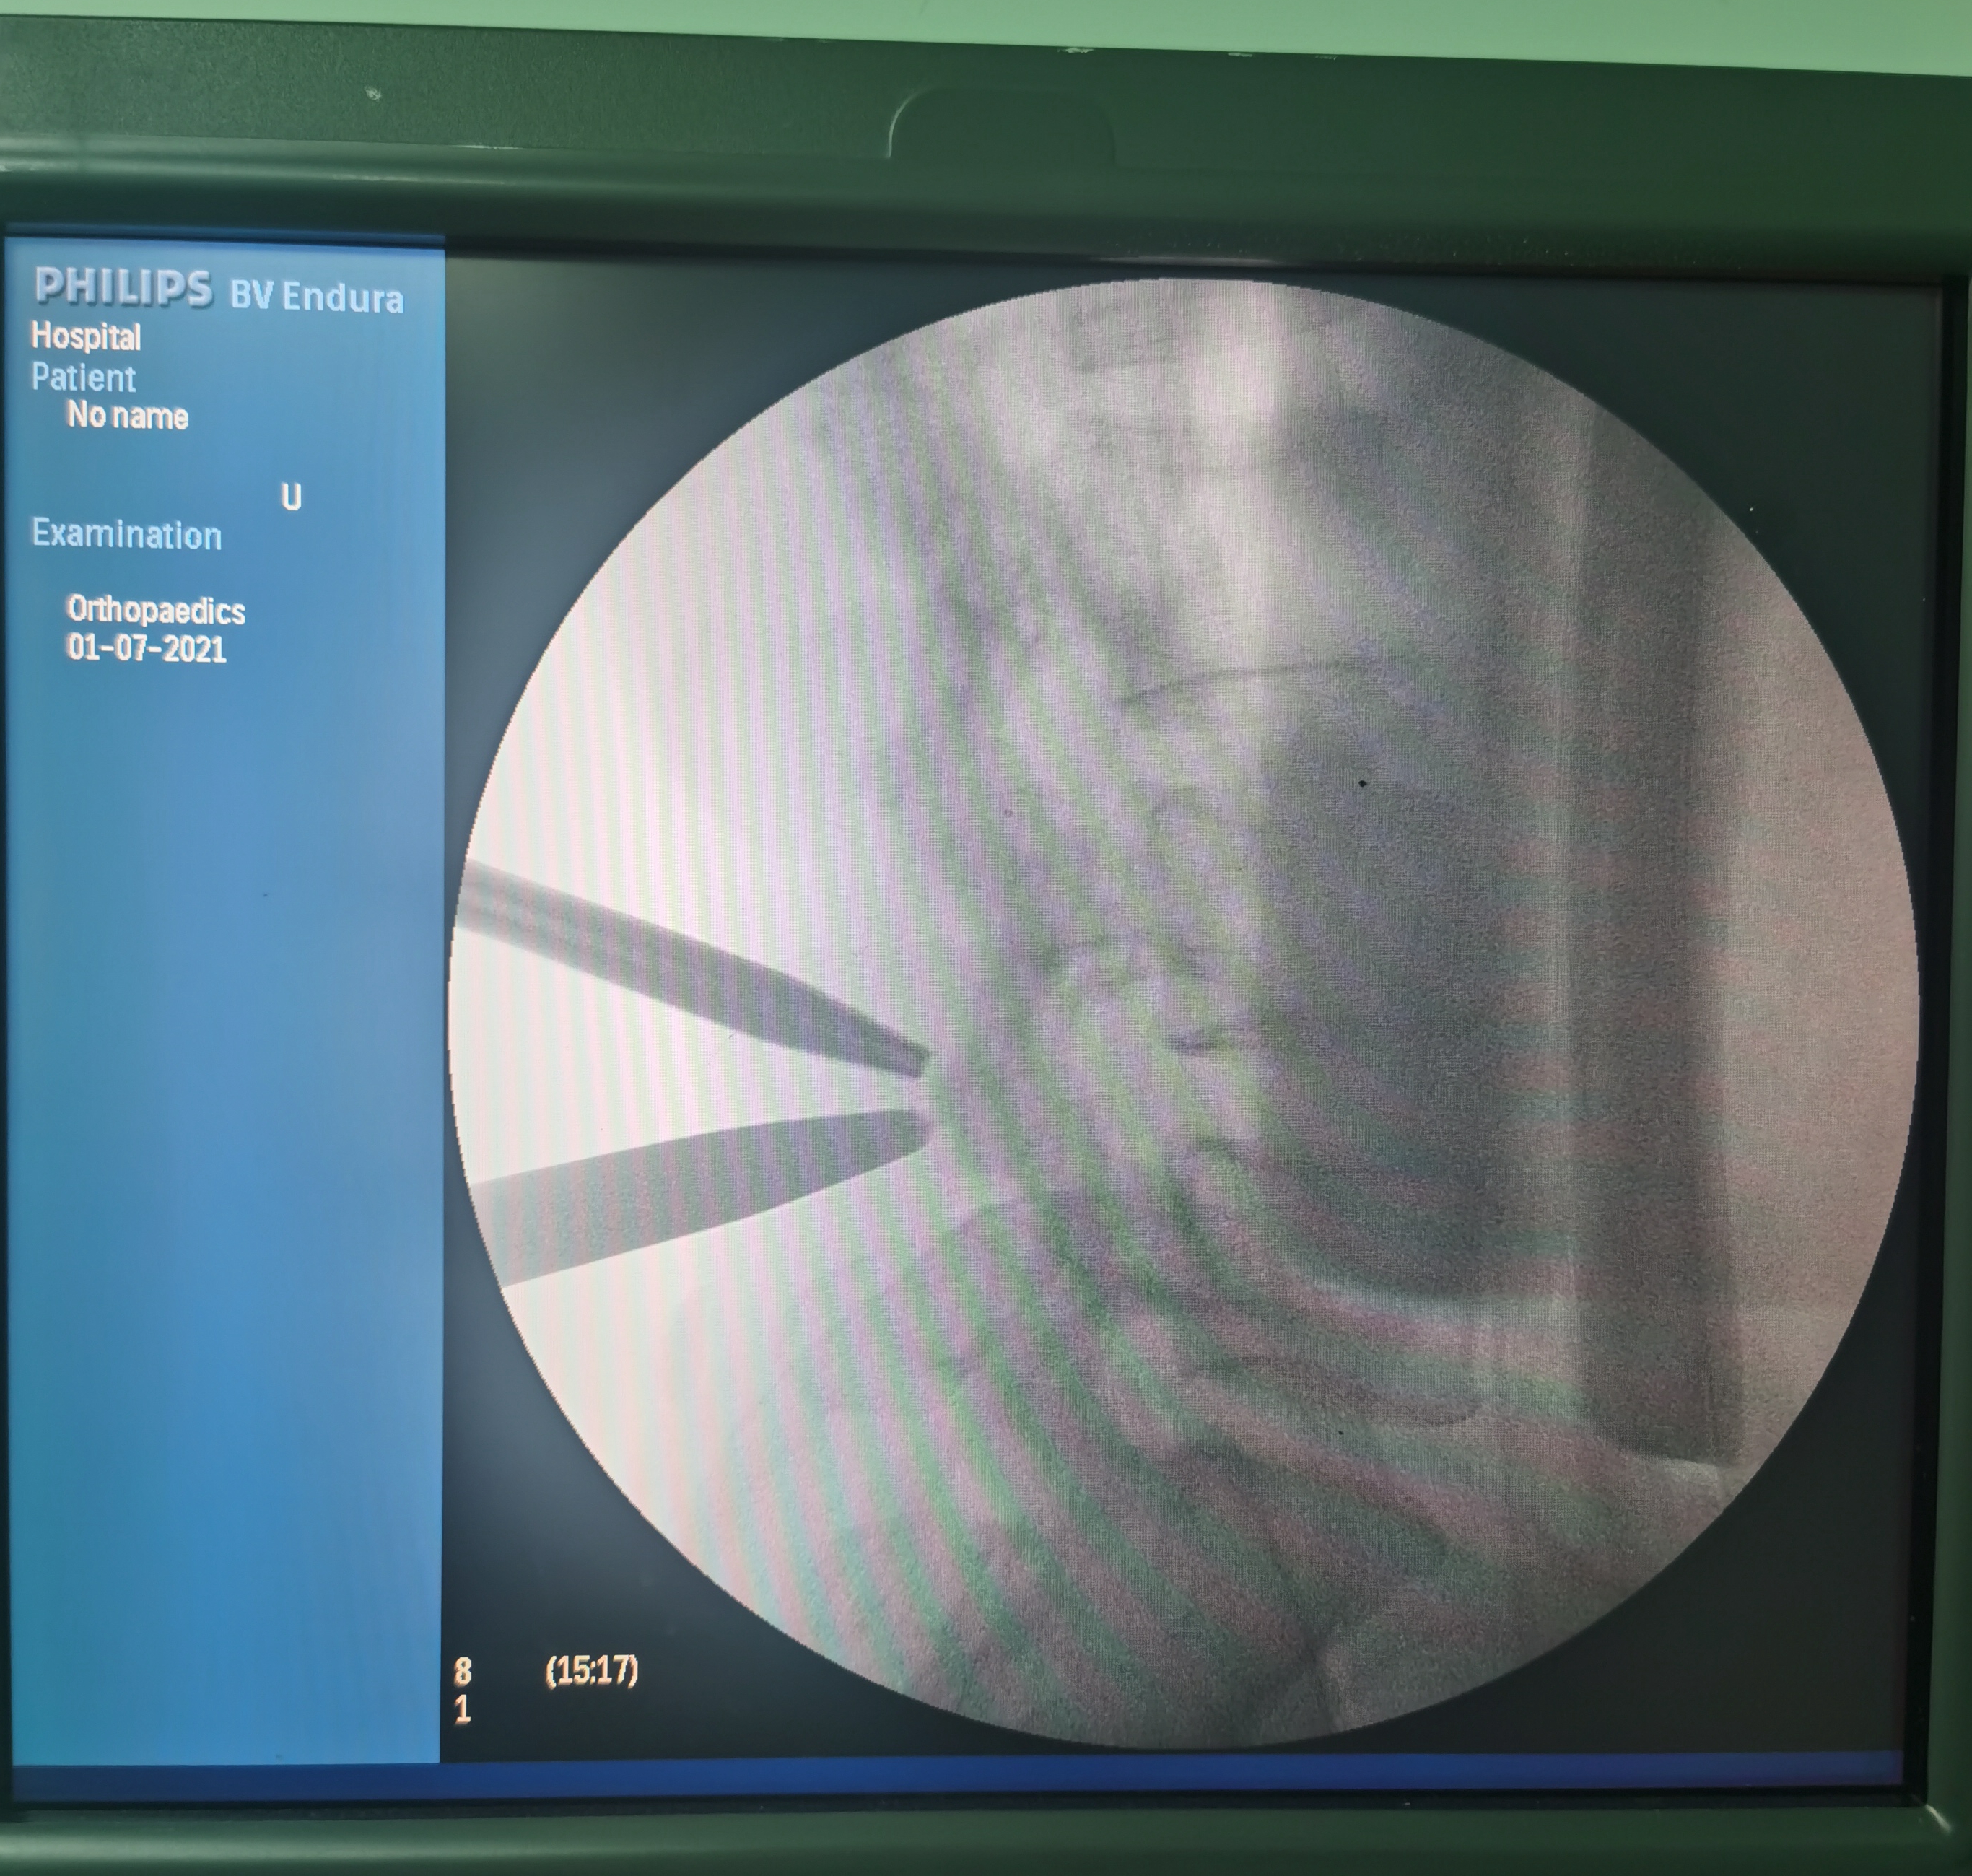

患者于7月1日在全麻下成功实施手术。术后第一天患者腰腿胀痛症状消失,麻木感明显好转,可在佩戴腰围后下地活动,于术后第4天顺利出院。